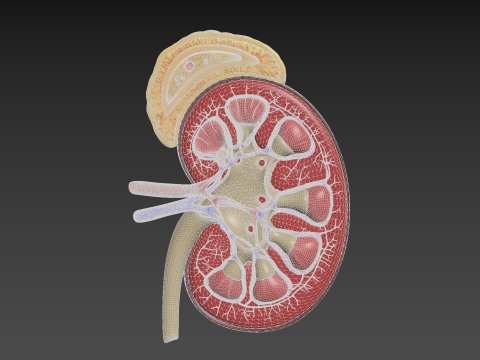

Human Kidney Low-poly Modelo 3D

- Polígonos:506522

- Vértices:366333

Human Kidney Modelo 3D blend, jpg, fbx, max, De jack2024

human kidney renal urine organ anatomical health people anatomy biology urinary system electrolytes internal organs science medical crossNo hay comentarios sobre este artículo.